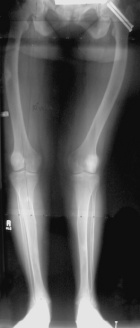

T.L. - 21 year old female presents with a one year hx of right thigh pain.

Zoom image: Radiological image Radiological image.